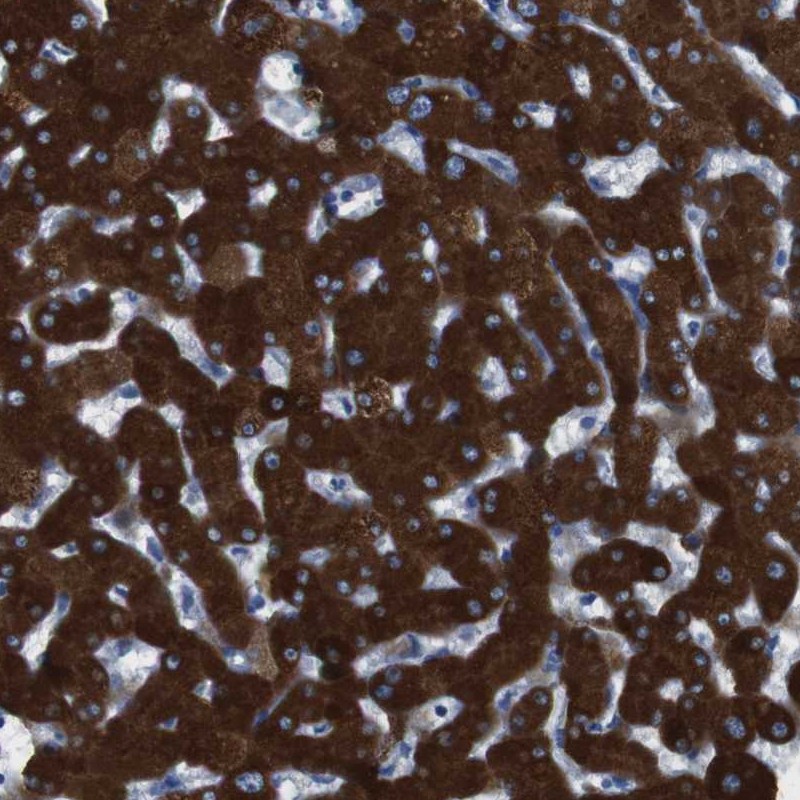

Immunohistochemical staining of human liver shows strong cytoplasmic positivity in hepatocytes.